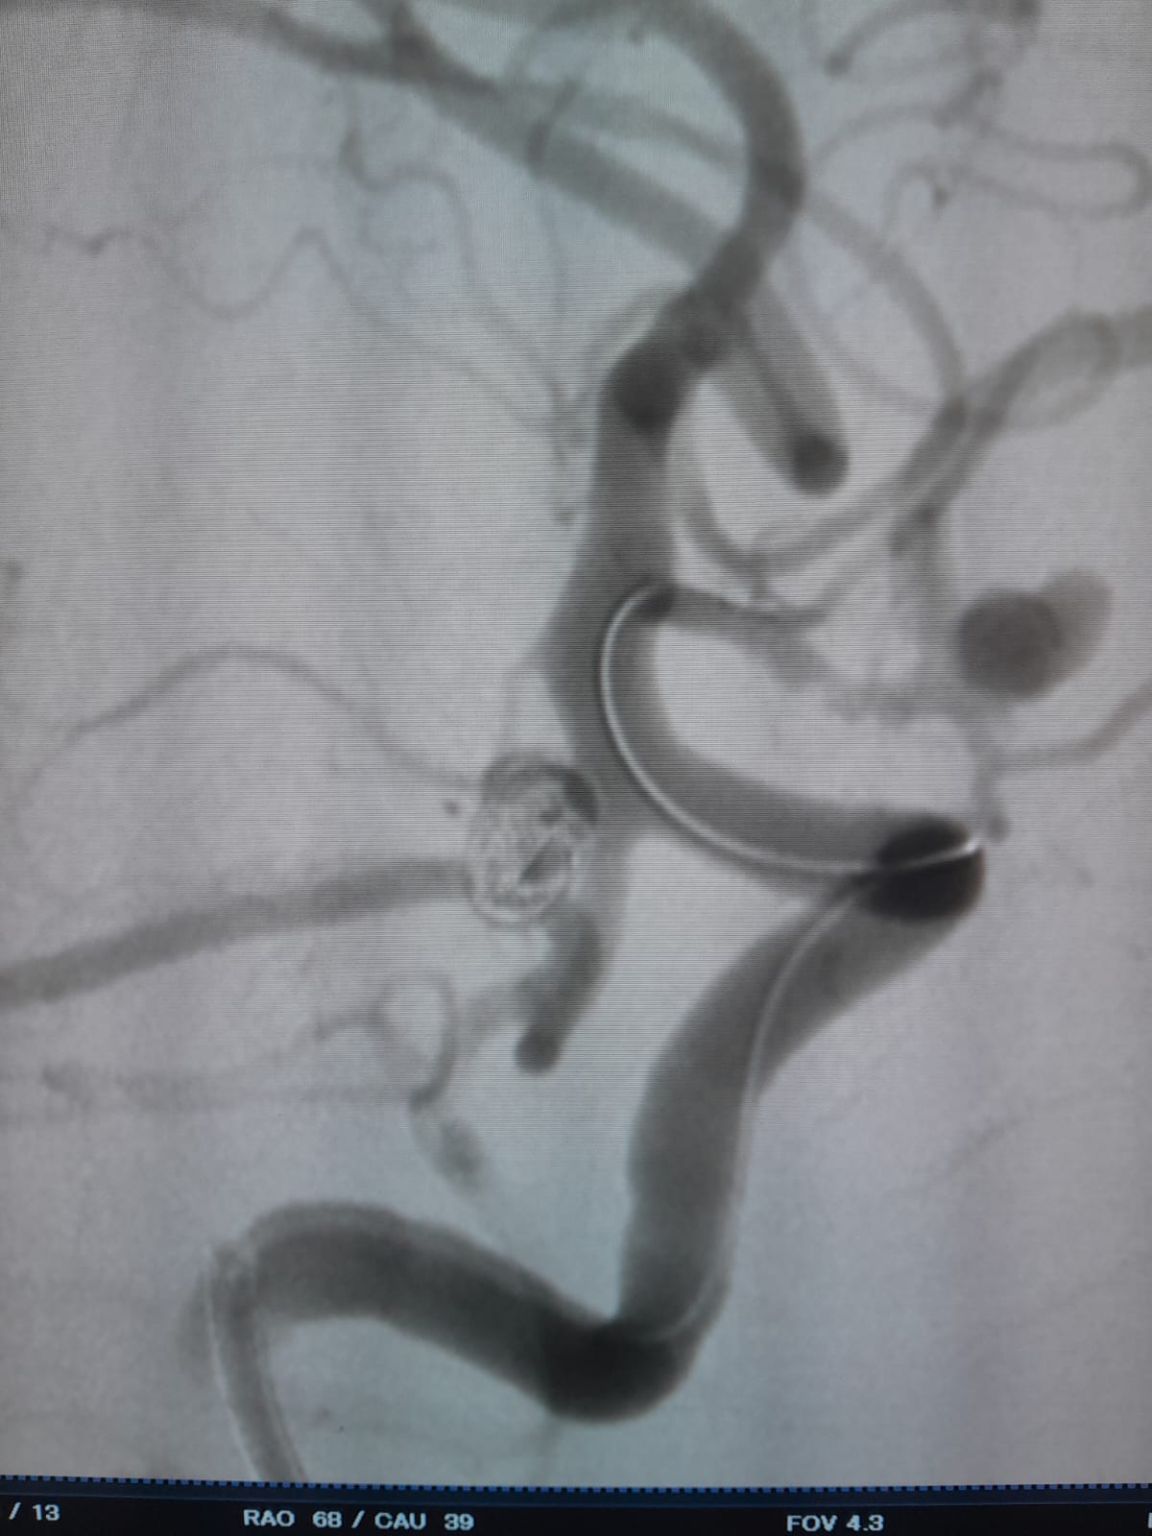

O acesso vascular foi estabelecido e a equipe então navegou com sucesso o Frepass®Microcateter descartável (TJMC14) para o local alvo. Embolização foi realizada utilizando três Perdenser®Embolic Coil System (TJCST4.508-3D, TJCST0306-3D, TJCST0206-3D) implantado com o Deromper®Bobina destacamento controlador (TJCDC).

Aneurisma Comunicando Artéria Posterior (Re-tratamento)

Durante o acompanhamento, observou-se enchimento residual no aneurisma da artéria comunicante posterior previamente tratado. A equipe acessou novamente o site usando o Frepass®Microcateter descartável (TJMC18 Plus) e implantado com sucesso um Nuva®Desvio do fluxo (TJED-D-4.5-16), que demonstrou a aposição ideal da parede e o desvio excelente do fluxo, conduzindo aos resultados altamente satisfatórios do tratamento.